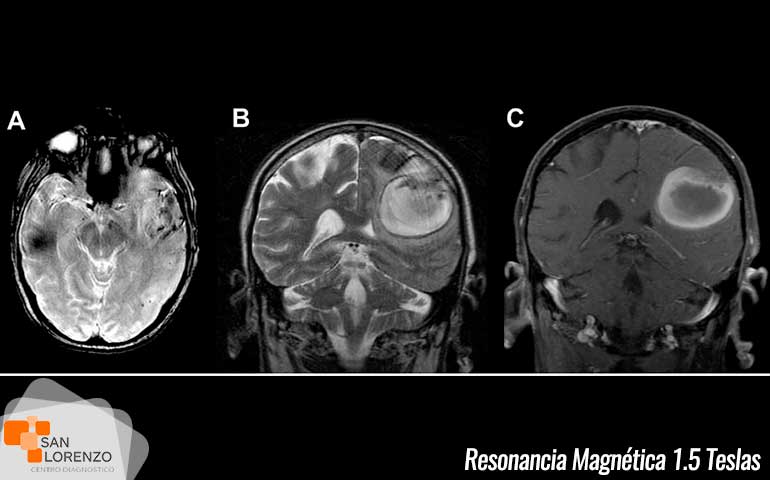

Desde sus inicios esta tecnología, Resonancia Magnética ha sido utilizada para el estudio del cerebro, la médula espinal, y la columna vertebral. Y a pesar que los primeros estudios de RM se realizaban de forma muy limitada, hoy en día la resonancia magnética de 1.5 o 3 teslas, permite el estudio de diferentes patologías, como la detección de tumores cerebrales, enfermedades neurodegenerativas, enfermedades al corazón, lesiones a la rodilla, o enfermedades a nivel osteoarticular por mencionar algunos alcances de este examen.

En simples palabras, una de las diferencias entre 1.5 Teslas y 3 Teslas en imagen médica, radica principalmente en la potencia de su campo magnético, lo que se traduce que mientras más elevado sean los Teslas, nos permite obtener información cada vez más detallada y sensible del cuerpo humano, mejorando el diagnóstico a cada paciente y aportando a médicos radiólogos y especialistas información más precisa sobre una enfermedad determinada.